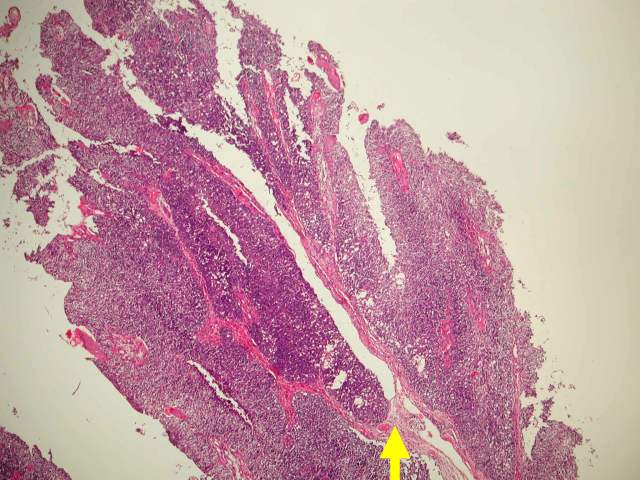

(Figure 2) Papillary transitional cell carcinoma with fibrovascular cores (arrow) lined by

carcinoma cells.